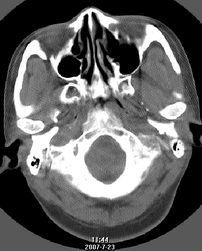

以下是引用还珠格格在2007-7-31 19:32:00的发言:[br]右侧鼻前庭内可见软组织块影,部分鼻中隔包绕其内,邻近骨质未见明显吸收破坏,考虑 1、鼻息肉可能性大 内翻乳头状廇不除外。期待结果。

以下是引用zjzjr在2007-7-31 20:29:00的发言:[br]右侧鼻前庭内可见软组织块影,部分鼻中隔包绕其内,邻近骨质未见明显吸收破坏,考虑 1、鼻息肉可能性大 内翻乳头状廇及肉芽肿类病变除外。期待结果。